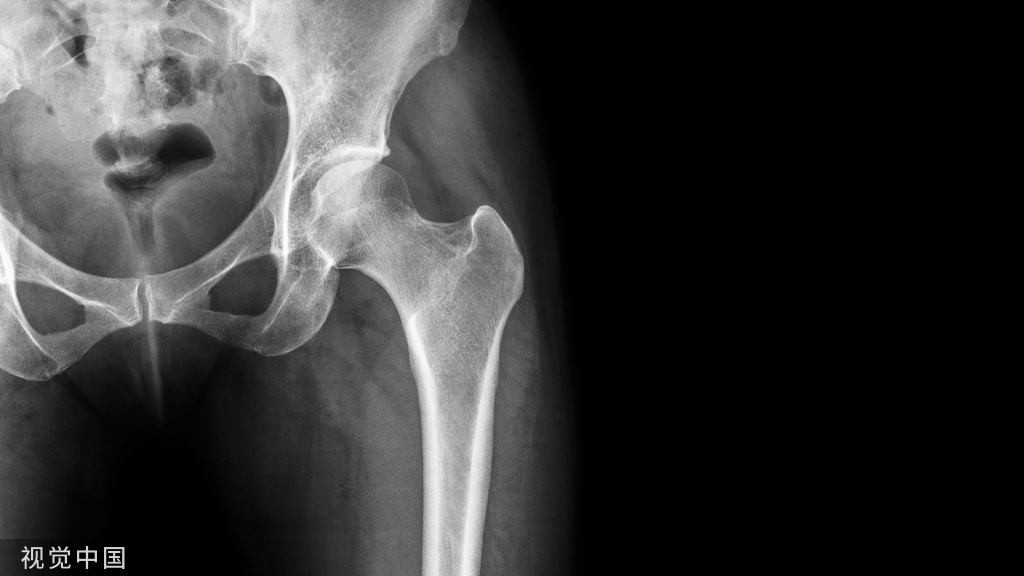

骨骼健康4要素: 成骨细胞、破骨细胞、钙剂、维生素D。 预防和抗骨质疏松治疗就需要围绕这4要素展开。

如何预防和治疗骨质疏松症,先把这幅图搬出来。

图源网络